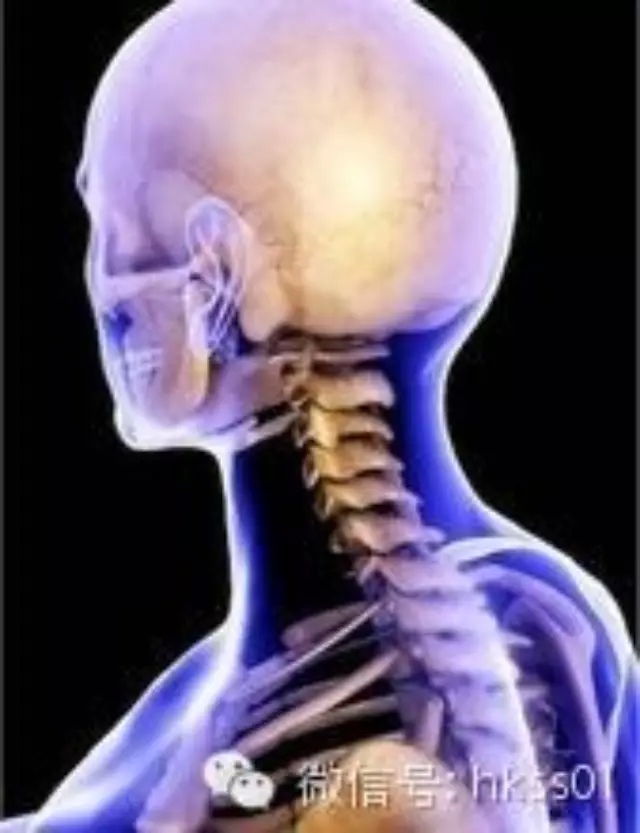

頸椎病對身體健康造成的十五大危害

危害一:中風

經中國醫學研究院不完全統計,中風病患者中有90%以上都有頸椎病,可怕的是很多人都不注意,到中風后才發現是頸椎病誘發了腦部神經壓迫導致了中風。

危害二:猝倒

主要是由于椎動脈壓迫所以引起,由于對頸椎健康的不重視很多患者被誤診為神經性偏頭痛,長時間得不到正確的治療嚴重的患者將導致腦淤血和突然猝倒。

危害三:腦梗塞、腦萎縮

很多頸椎病患者因椎動脈痙攣、栓塞、而誘發為腦梗塞、腦萎縮等疾病。

危害四:癱瘓

有很多頸椎病患者對頸椎病的認識不足,不重視,由于得不到及時治療,頸椎病變造成脊髓、神經等的刺激與壓迫就很容易導致單側或雙側上肢癱瘓或大小便失禁。